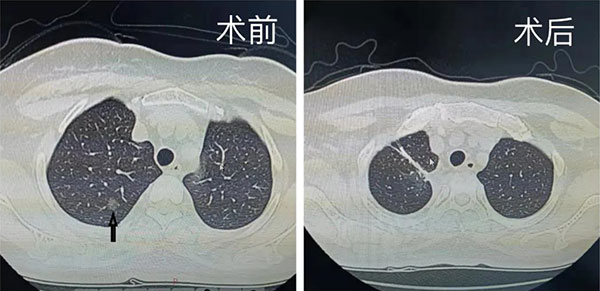

一例中年女性患者,CT的结果显示:右肺上叶一个磨玻璃结节,位于右肺上叶尖段和后段交界处。这样的病例要是进行肺叶切除则肺损伤过多,若行常规的肺段切除,那么无论是切除尖段还是后段,恐怕切缘范围都难以保证。在微创诊疗中心主任刘树库的带领下,团队最终制定了对胸腔镜单操作孔右肺上叶尖段A亚段合并右肺上叶后段A亚段切除的措施,并顺利完成手术。术后在全体医护人员的精心呵护下,患者快速恢复,顺利出院。